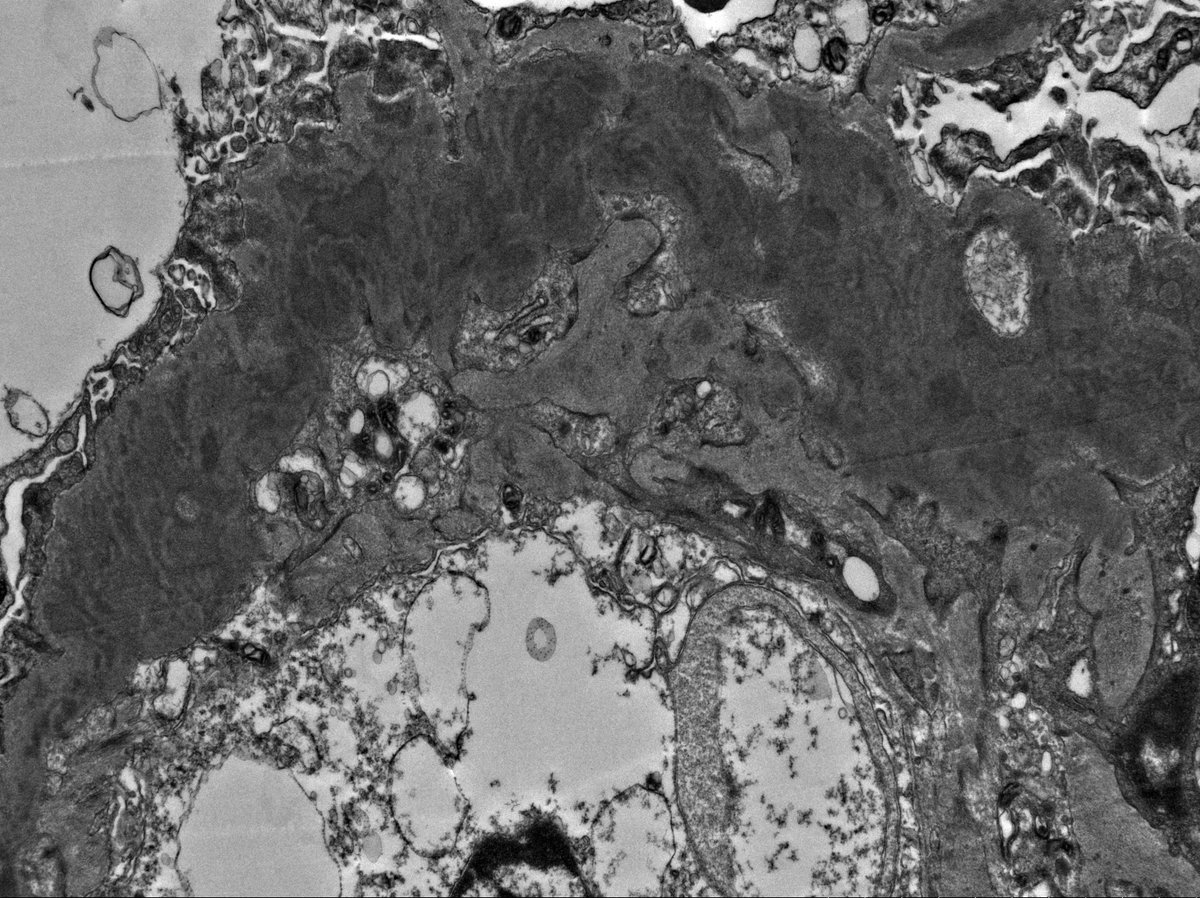

C3 GN in 11 yo boy with proteinuria, hypertension, low C3 (normal C4). EM shows irregular thickening of glomerular capillary wall and mesangial expansion by electron dense deposits. The deposits are somewhat ill-defined with early sign of resorption.